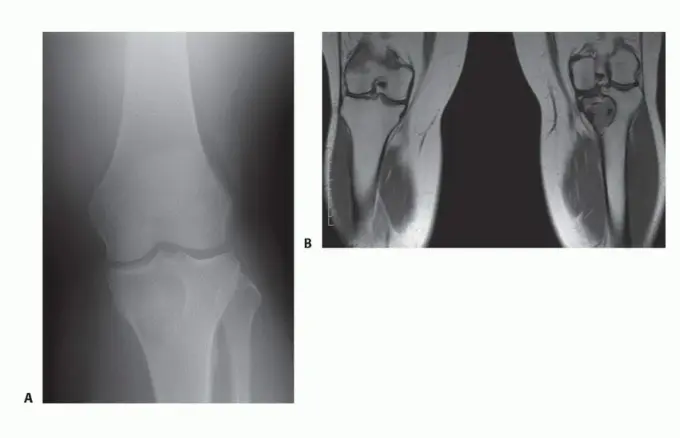

- التقييم الشامل: يقوم الدكتور هطيف بإجراء تقييم سريري دقيق، ومراجعة التاريخ المرضي للمريض، وإجراء الفحوصات التصويرية اللازمة (الأشعة السينية، الرنين المغناطيسي، الأشعة المقطعية، ومسح العظام) لتحديد حجم الورم وموقعه وعلاقته بالهياكل الحيوية المحيطة.

- الخزعة (Biopsy): في معظم الحالات، يتم أخذ خزعة من الورم لتأكيد التشخيص النسيجي وتحديد ما إذا كان حميدًا أو خبيثًا.